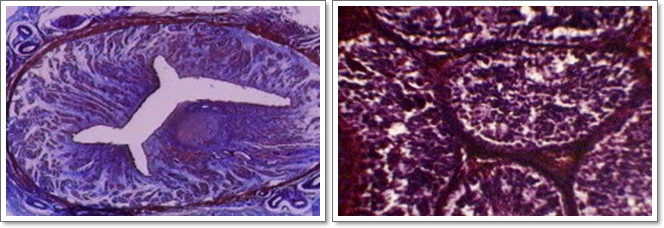

Trompa uterina És un conducte d'una llargària de diversos centímetres, que té la missió de transportar els òvuls madurs fins a l' úter gràcies a nombrosos cilis mòbils que entapissen la paret interna. És interessant fer constar que la fecundació es produeix sempre dins les trompes, i no dins l'úter; l'òvul fecundat segueix el camí vers l'úter, i es fixa a l' endometri (la paret interna), originant l'òrgan de connexió amb la mare, que és la placenta. (abaix esquerra)

Testicle de porc Exemple representatiu de gònada masculina, perquè l'estructura dels testicles de tots els mamífers és similar i dissenyada a base de tres parts diferenciades: una coberta fibrosa i resistent, centenars o milers de conductes seminífers encarregats de la producció dels espermatozoides, que es troben en gran quantitat i envoltats, i l'estroma, que és un teixitconjuntiu lax molt vascularitzat. Les cèlúlules intersticials tenen funció endocrina i produeixen l'hormona masculina anomenada testosterona (Dalt dreta)

Epidídim de porc És el conducte encarregat de completar la maduració dels espermatozoides, que avancen lentament a mida que experimenten el procés. Té, igual que el testicle -al qual està aferrat-, una coberta fibrosa, i acaba al principi del conducte deferent, que duu els espermatozoides fins a les vesícules seminals, per constituir la base de l' ejaculació Com a dada curiosa podem dir que el volum del líquid de l'ejaculació de l'home i del toro és normalment de 3-3,5 cc, mentre que en el porc és de 250 cc (Baix esquerra)

Ovari d'ovella És el lloc de formació dels òvuls, és a dir, la gònada femenina, i està constitu‹t per dues zones diferenciades: la zona medulúlar, molt rica en vasos sanguinis, i la zona cortical, on es poden apreciar gran quantitat de folúlicles de Graaf, que són els llocs on es desenvolupen els òvuls. (Dalt dreta).